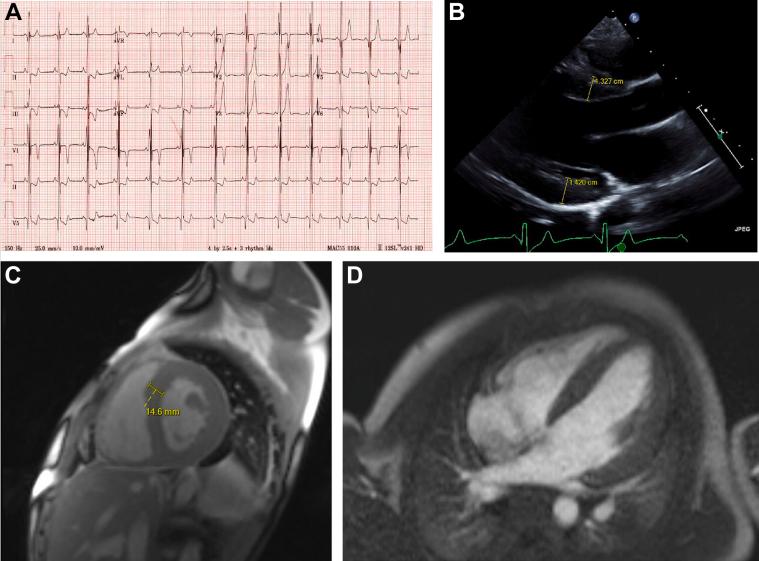

Unmasking Primary Carnitine Deficiency as a Mimic of Hypertrophic Cardiomyopathy.

Primary carnitine deficiency may mimic hypertrophic cardiomyopathy and be mistakenly attributed to genotype-negative sarcomeric protein dysfunction in hypertrophic cardiomyopathy. Although rare, timely diagnosis may have significant implications on management and should prompt testing of family members.